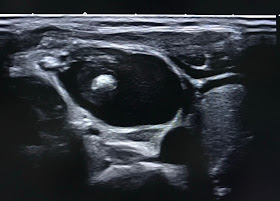

ULTRASOUND OF THE NECK SHOWS THYROID IS NORMAL, and   CYSTIC MASS LOCATED AT LATERAL OF RIGHT NECK   ALONG OF SCM MUSCLE.

US1= (CROSSED SECTION)